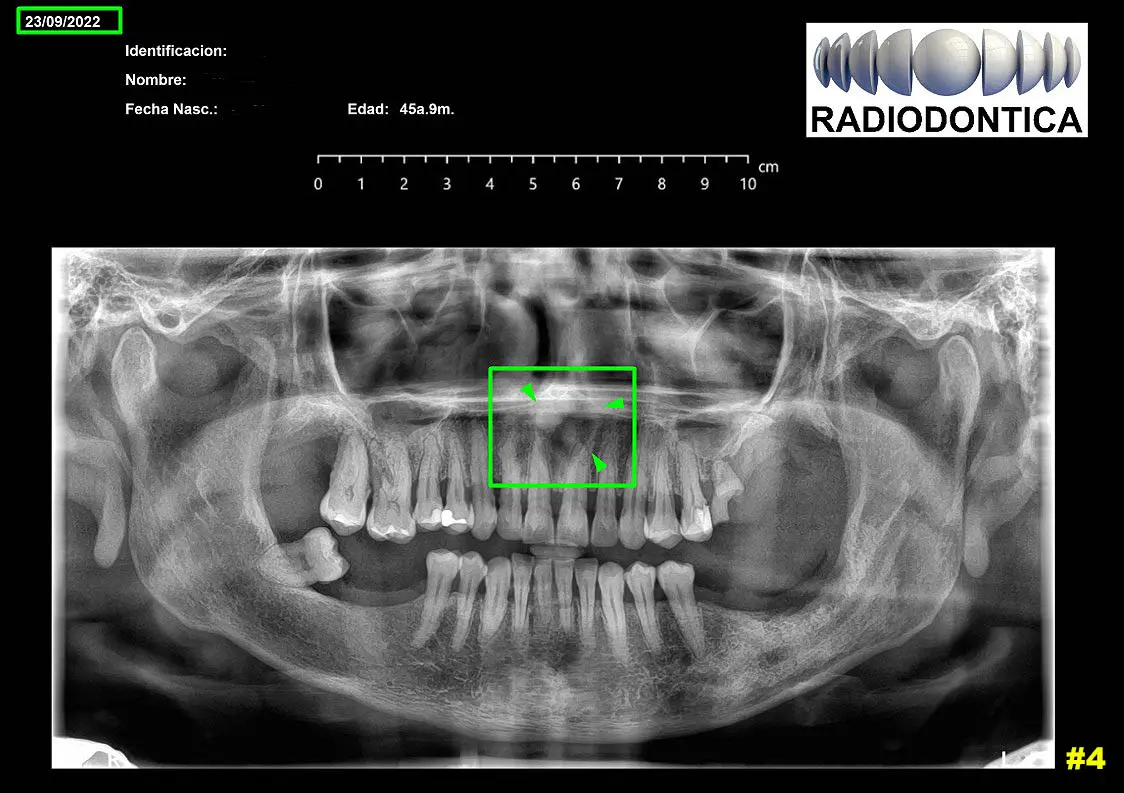

-Rx panorámica realizada en septiembre 2022, donde se observan en zona anterior entre Pd 11 – Pd 21 imagen radiolúcida con forma semicircular no bien definida. Imagen 4